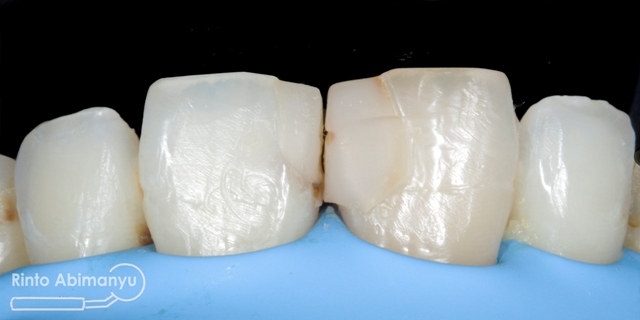

Tampak depan sebelum tambalan dibongkar

Tambalan lama dibongkar dan seluruh jaringan karies sekunder dibuang, kemudian tepi kavitas labial dibuatkan bevel…

Setelah tambalan dibongkar dan dibuatkan bevel